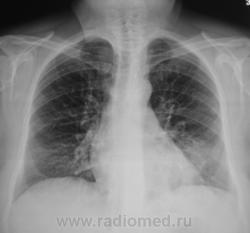

Пациент направлен на рентгенографию ОГК с диагнозом – «левосторонняя пневмония».

Мне этот кругляк мерещится?

Так еще один кругляк, на прямой рентгенограмме, слева в третьем межреберье визуализируется.